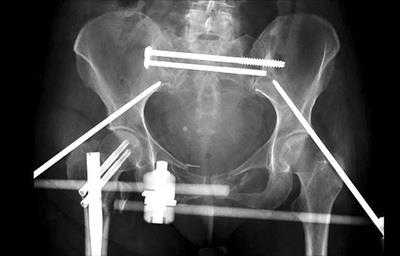

Наружная фиксация. Наружная фиксация применяется для стабилизации тазового кольца. Операция заключается во введении через небольшие кожные разрезы и мышцы в кости таза металлических стержней или винтов. Концы этих стержней и винтов остаются над поверхностью кожи по обе стороны таза и фиксируются к карбоновым соединительным балкам. Наружный фиксатор выполняет роль стабилизирующей рамки, удерживающей кости таза в правильном положении.

В некоторых случаях наружный фиксатор применяется для стабилизации вплоть до наступления сращения перелома. У пациентов, которые на данный момент по состоянию здоровья не могут перенести более продолжительное и сложное хирургическое вмешательство, которое им показано, наружный фиксатор может использоваться в качестве временной меры, используемой до момента стабилизации состояния пациента и выполнения окончательной фиксации перелома.

В данном случае для стабилизации костей таза использован наружный фиксатор.